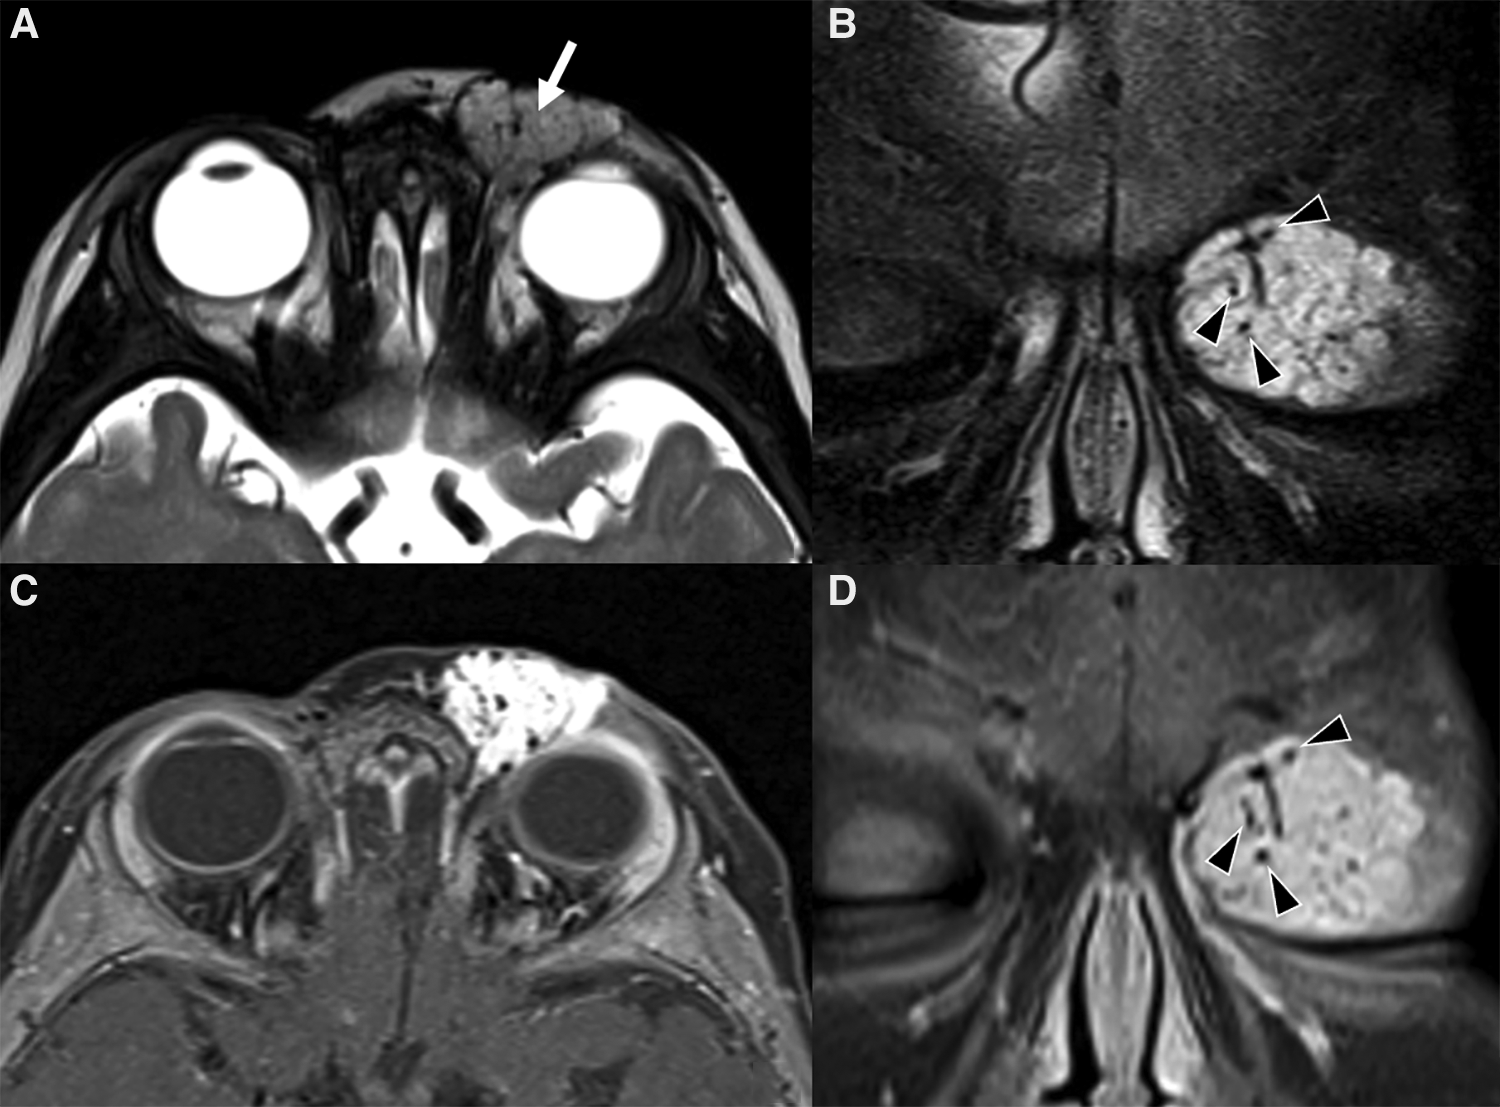

On the other hand, it is MRI that provides the best insights on the architecture and the best accuracy on the extension and spatial relationships of the lesion. Indeed, it may show the tumor involving and enlarging the eyelid and obstructing vision, displacing or distorting the globe or the extra- ocular muscles. On T2w images hemangiomas appear as a well-defined, lobulated and hyperintense masses with flow-voids and thin, dark septa between lobules (Figure 4). These features are even more striking on STIR images (Figure 4). Flow voids are less likely seen in the involuting and involuted phase. On T1w sequences they show a heterogeneous low/intermediate signal with a variable amount of hyperintensity related to fat tissue deposits according to the evolutionary phase. Contrast enhancement is usually homogeneous and intense during the proliferative phase (Figures 4, 5), although it may become less homogenous, intense and predictable in the involuting and involuted phase.

Figure 4. Mr images of a non-syndromic left periorbital infantile hemangioma in a 1-year-old girl. Axial (A) and coronal fat-saturated (B) T2 weight images show a well-defined hyperintense mass (arrow in A) with multiple internal flow voids (black arrowheads in B and D), extending from the anterior periorbital soft tissues into the extra and intraconal compartments of the orbit. Axial (C) and coronal (D) contrast-enhanced fat-saturated T1 weighted images show vivid homogeneous contrast enhancement of the vascular lesion.

Figure 5. Mr images of a 6-month-old girl with known PHACES. Axial T2 (A) and contrast-enhanced T1 weighted images (B,C) show a diffuse segmental hemangioma of the right orbital, malar and auricular regions. Coronal dynamic MR angiography during gadolinium injection (D–F) shows the “progressive filling” of the vascular lesion. Also note in (C) the small enhancing mass in the right internal auditory canal (white arrow), consistent with an intracranial hemangioma, and the ipsilateral cerebellar hypoplasia.